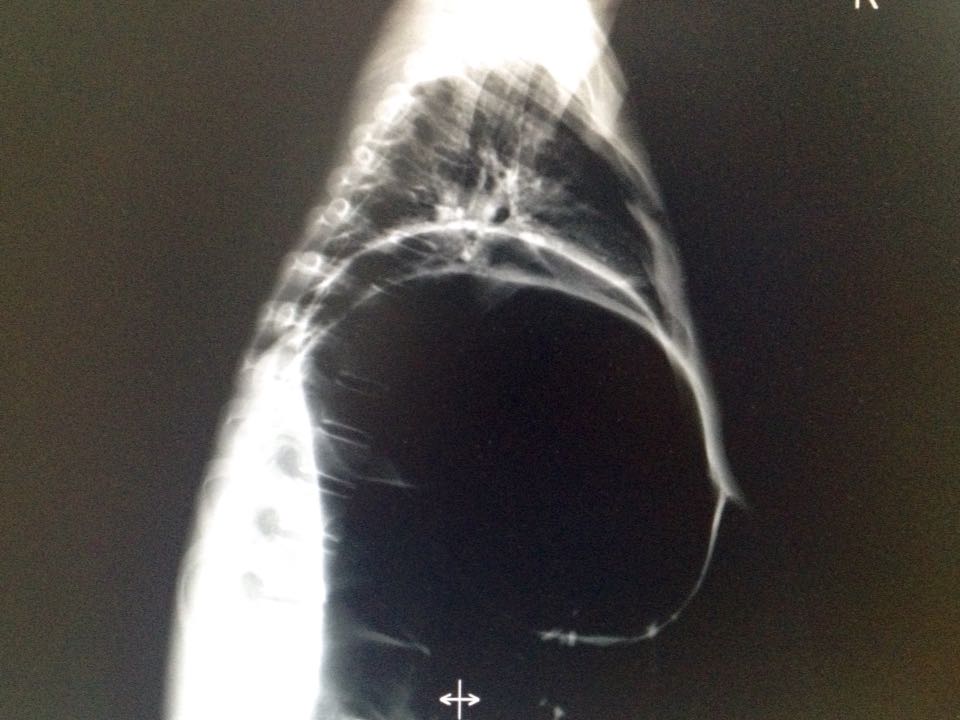

惊呆了!你可能未见过的片子。

19岁男孩 间断腹痛2年 如图,猜猜什么病?